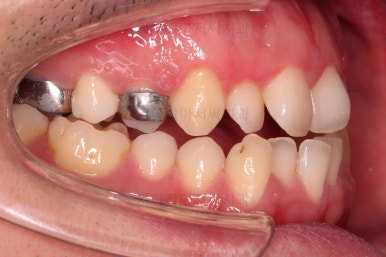

초진 시 입안의 모습입니다.

교합이 많이 안좋습니다.

위아랫니가 서로 엇갈려 가며 지그재그로 껴 들어가야 어금니 맞물림이 생기는데요.

이번 환자분은 아랫니, 아래턱이 전반적으로 앞으로 나와 있어서 교합이 전혀 안되고 있는 상태였습니다.